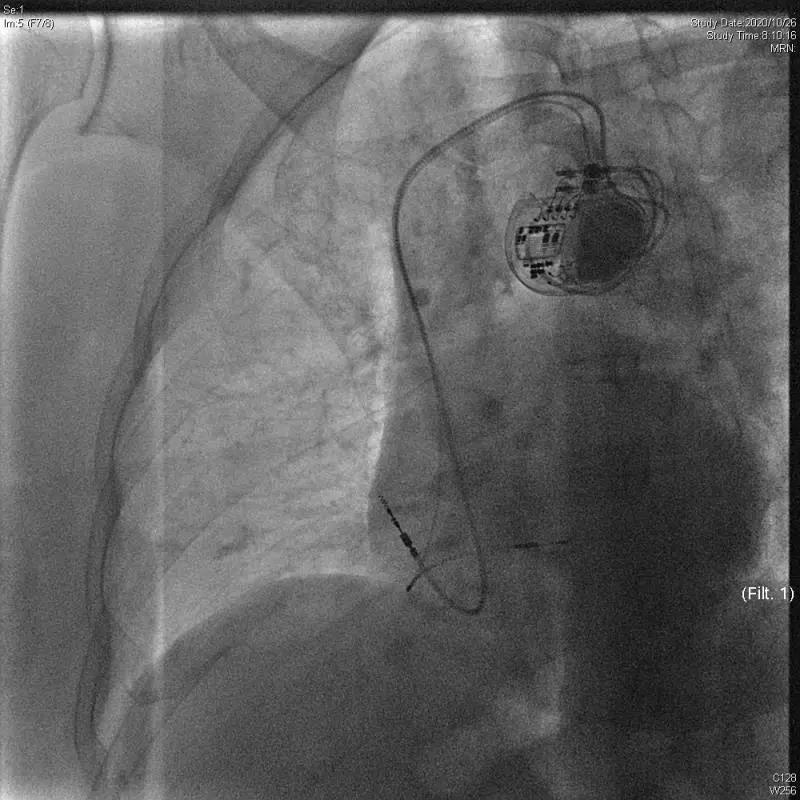

北京清华长庚医院10月26日电(心脏内科 刘元伟 何榕)10月26日,北京清华长庚医院心内科何榕医师、刘元伟医师带领团队,在副院长张萍教授的指导下,顺利植入了全国首台3.0T核磁兼容长寿命新型双腔起搏器(Astra)。

该患者为70岁女性,因III度房室传导阻滞、头晕、黑曚入院,心室率仅30-40次/分。同时伴有双手震颤、麻木、腔隙性脑梗、骨关节病等,后期明确有3.0T场强MRI检查的需求。另外,患者高龄,要求植入长寿命起搏器以减少后期器械更换次数,降低感染风险。正值3.0T长寿命起搏器刚刚进入国内,综上考虑选择植入Astra双腔起搏器。此外,患者为III度房室传导阻滞,心室起搏依赖,为避免长期右室起搏导致心功能不全,决定采用国际先进的左束支区域起搏技术。

手术过程顺利,术后起搏心电图QRS时限仅112ms,患者症状即刻缓解,手术效果良好。